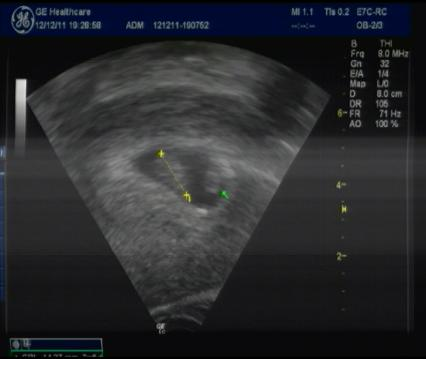

Dám vám sem fotečku,ale je tam jen takový flek.Jen mi holky řekněte,co je to v pravo jak je tam ta zelená šipka u toho